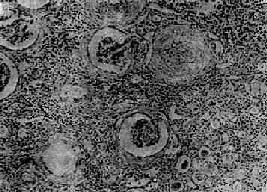

图12-25 慢性肾盂肾炎

有些肾小球毛细血管丛相对正常,肾球囊壁增厚,纤维化,部分肾小管萎缩消失,部分肾小管扩张,腔内有胶样管型;间质纤维组织增生,有大量淋巴细胞等炎细胞浸润